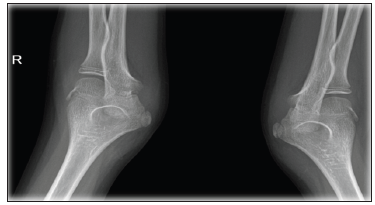

A 12-year-old Saudi boy born to consanguineous parents and presented to Pediatric hematology clinic with intermittent joint swelling for 2 years. He was previously diagnosed as Factor VII deficiency at another hospital and received recombinant Factor VII replacement for unknown period with no significant improvement. Local examination showed painful swelling of bilateral elbow joints and right ankle joint with restricted range of movements and overlying skin redness. Mild muscle wasting was also noticed (Figure 1). Furthermore, patient was circumcised at the age of 1 month, and multiple tooth extractions were done before 10 years of age without any significant bleeding [1]. Laboratory findings showed low hemoglobin (10.7g/dl) with deranged bleeding profile and factor VII deficiency. Radiological examination showed marked effusion of bilateral elbow joints and right ankle joint with left elbow extraarticular synovial cyst (Figure 2).

Figure 2: X-Ray of both elbows showed marked swelling of both joint with erosion.